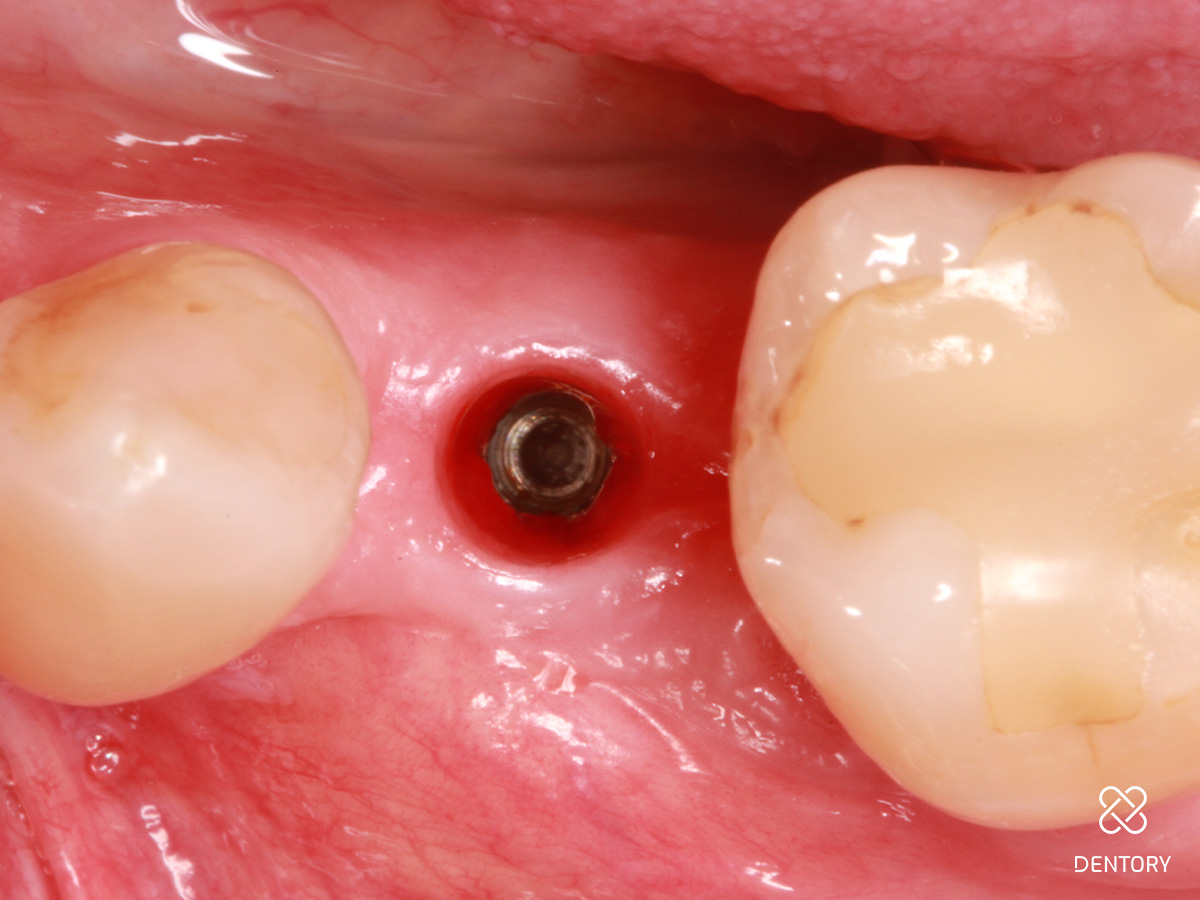

Abbildung 3

Okklusale Ansicht nach Insertion eines 4 mm-Implantats mit Plattform-Switching. Eine simultane Defektrekonstruktion erscheint möglich.